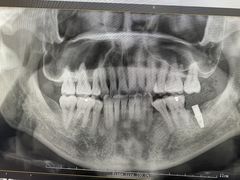

点小评5596777448 | 22-02-22

报错

• -牙博士口腔品牌连锁(杨浦店)